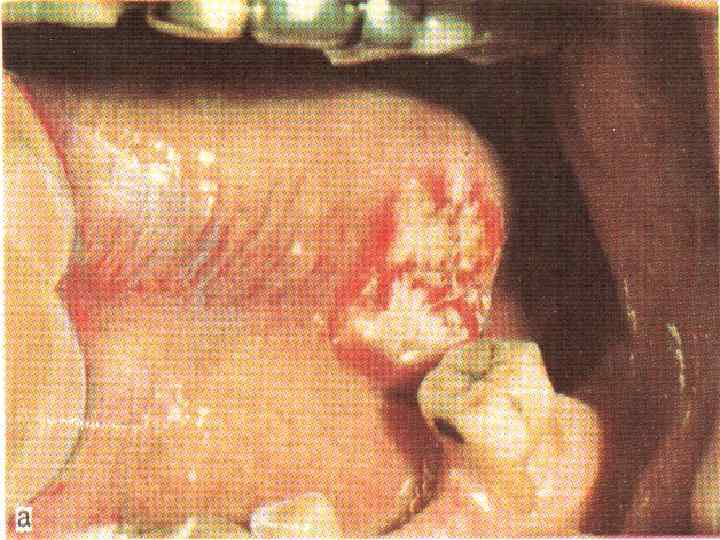

Рак языка (экзофитная форма)

Рак языка (экзофитная форма)